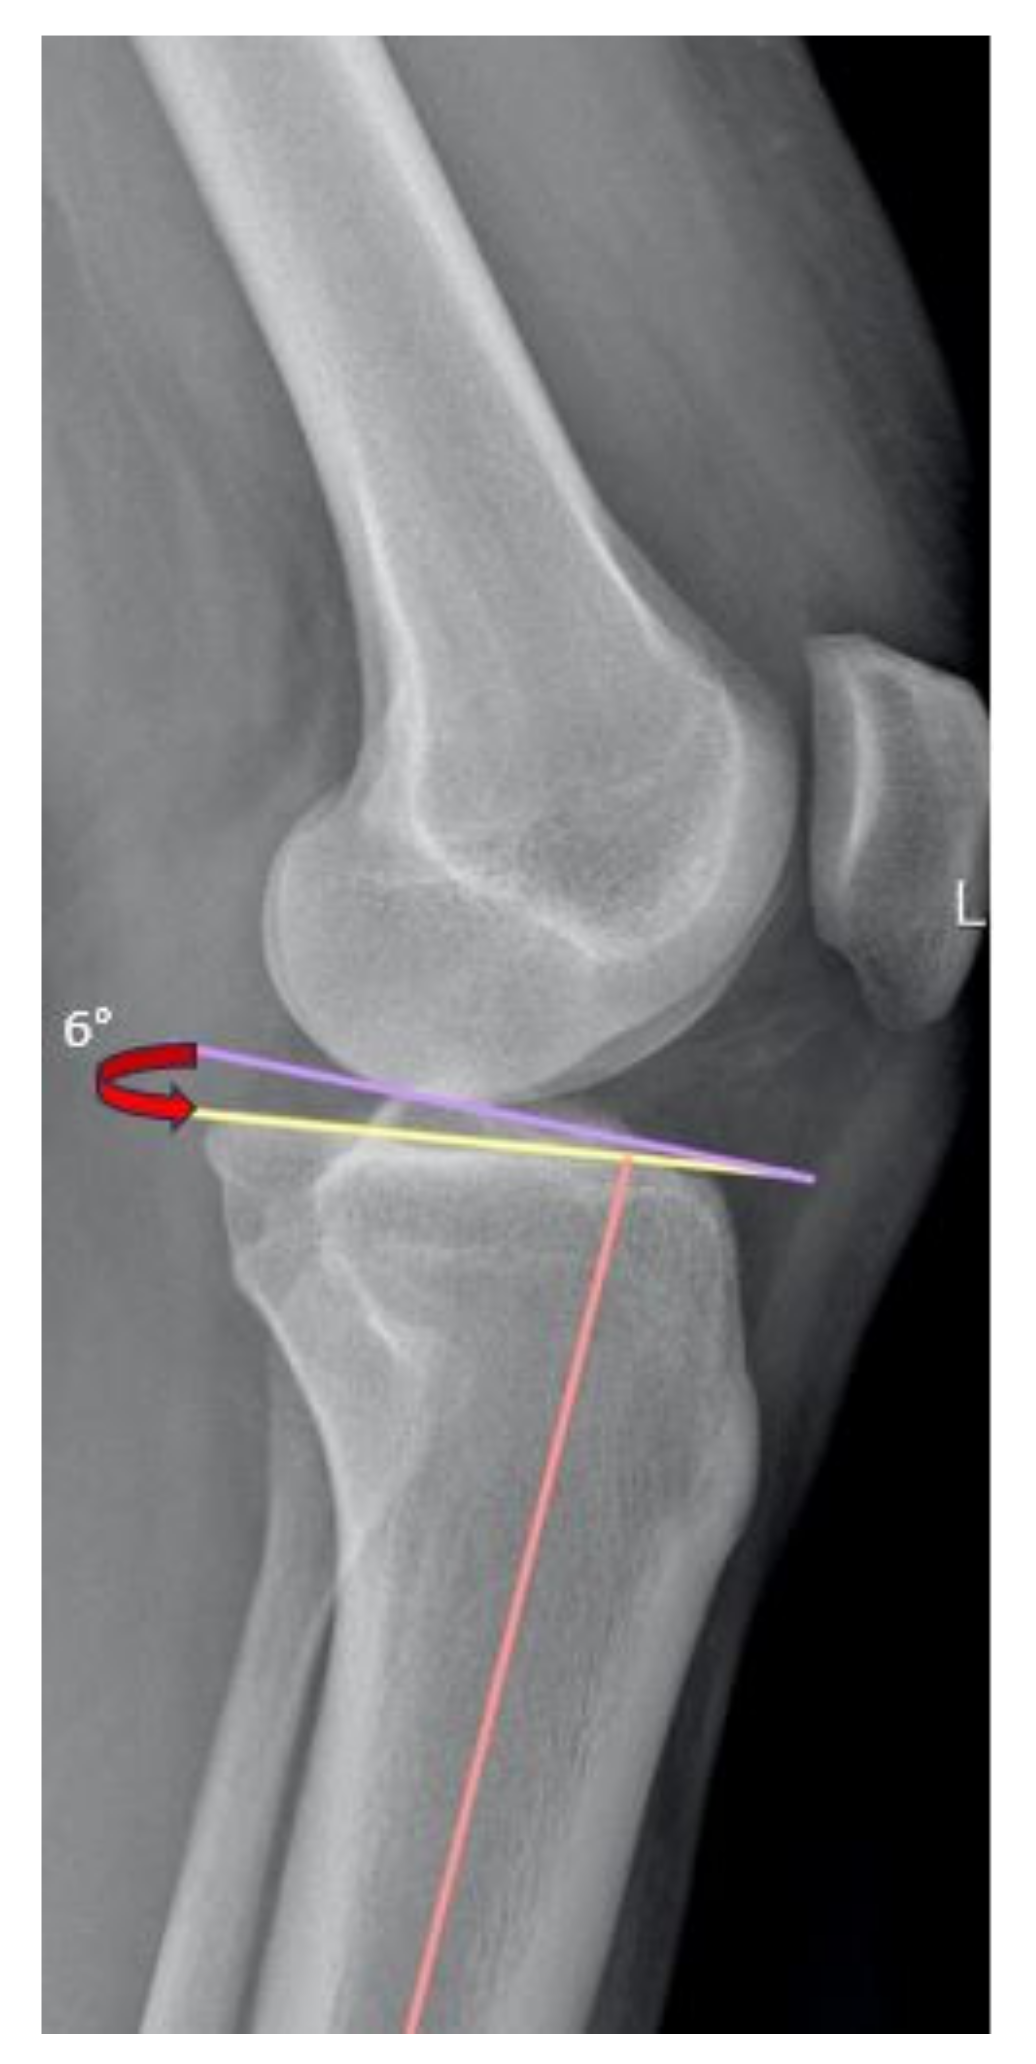

2.4. Radiological Assessment

| Posterior tibial slope | 6.7 ± 1.8 (2.5–10.4) |

| Posterior tibial slope | 6.5 ± 1.7 (3.7–9.7) | 7 ± 1.9 (2.5–10.4) | 0.192 | −1.255 to 0.255 | 0.380 |